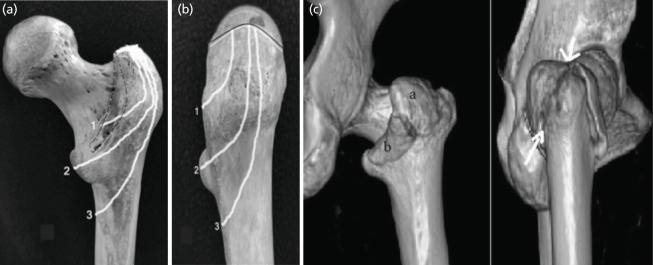

Introduction: The Intertrochanteric fracture is a common hip trauma encountered in elderly patients. There is a lack of general agreement regarding its surgical management and choice of implant. Purpose of this study to conclude the final decision matrix regarding surgical management of intertrochanteric fractures based on parameters assessed on plain radiographs and CT scan.

Materials and methods: We have retrospectively evaluated 55 patients with intertrochanteric fractures presented to our institute after informed consent with radiographs and CT scans between July 2017 to July 2018. Assessment of various parameters regarding fracture geometry and classification as well as measurement was done.

Results: Mean lateral wall thickness in present study was 20.76mm. Incidence of coronal fragments was 90.9% and absence of coronal fragment in 5 patients. We noted the cases with anterior comminution had also a posterior comminution rendered the fracture unstable in almost 20 % cases.

Conclusion: Better understanding of fracture geometry by combined used of radiograph and CT scan enhanced preoperative planning, choice of suitable implant, helps in reduction manoeuvre and improving quality of osteosynthesis.